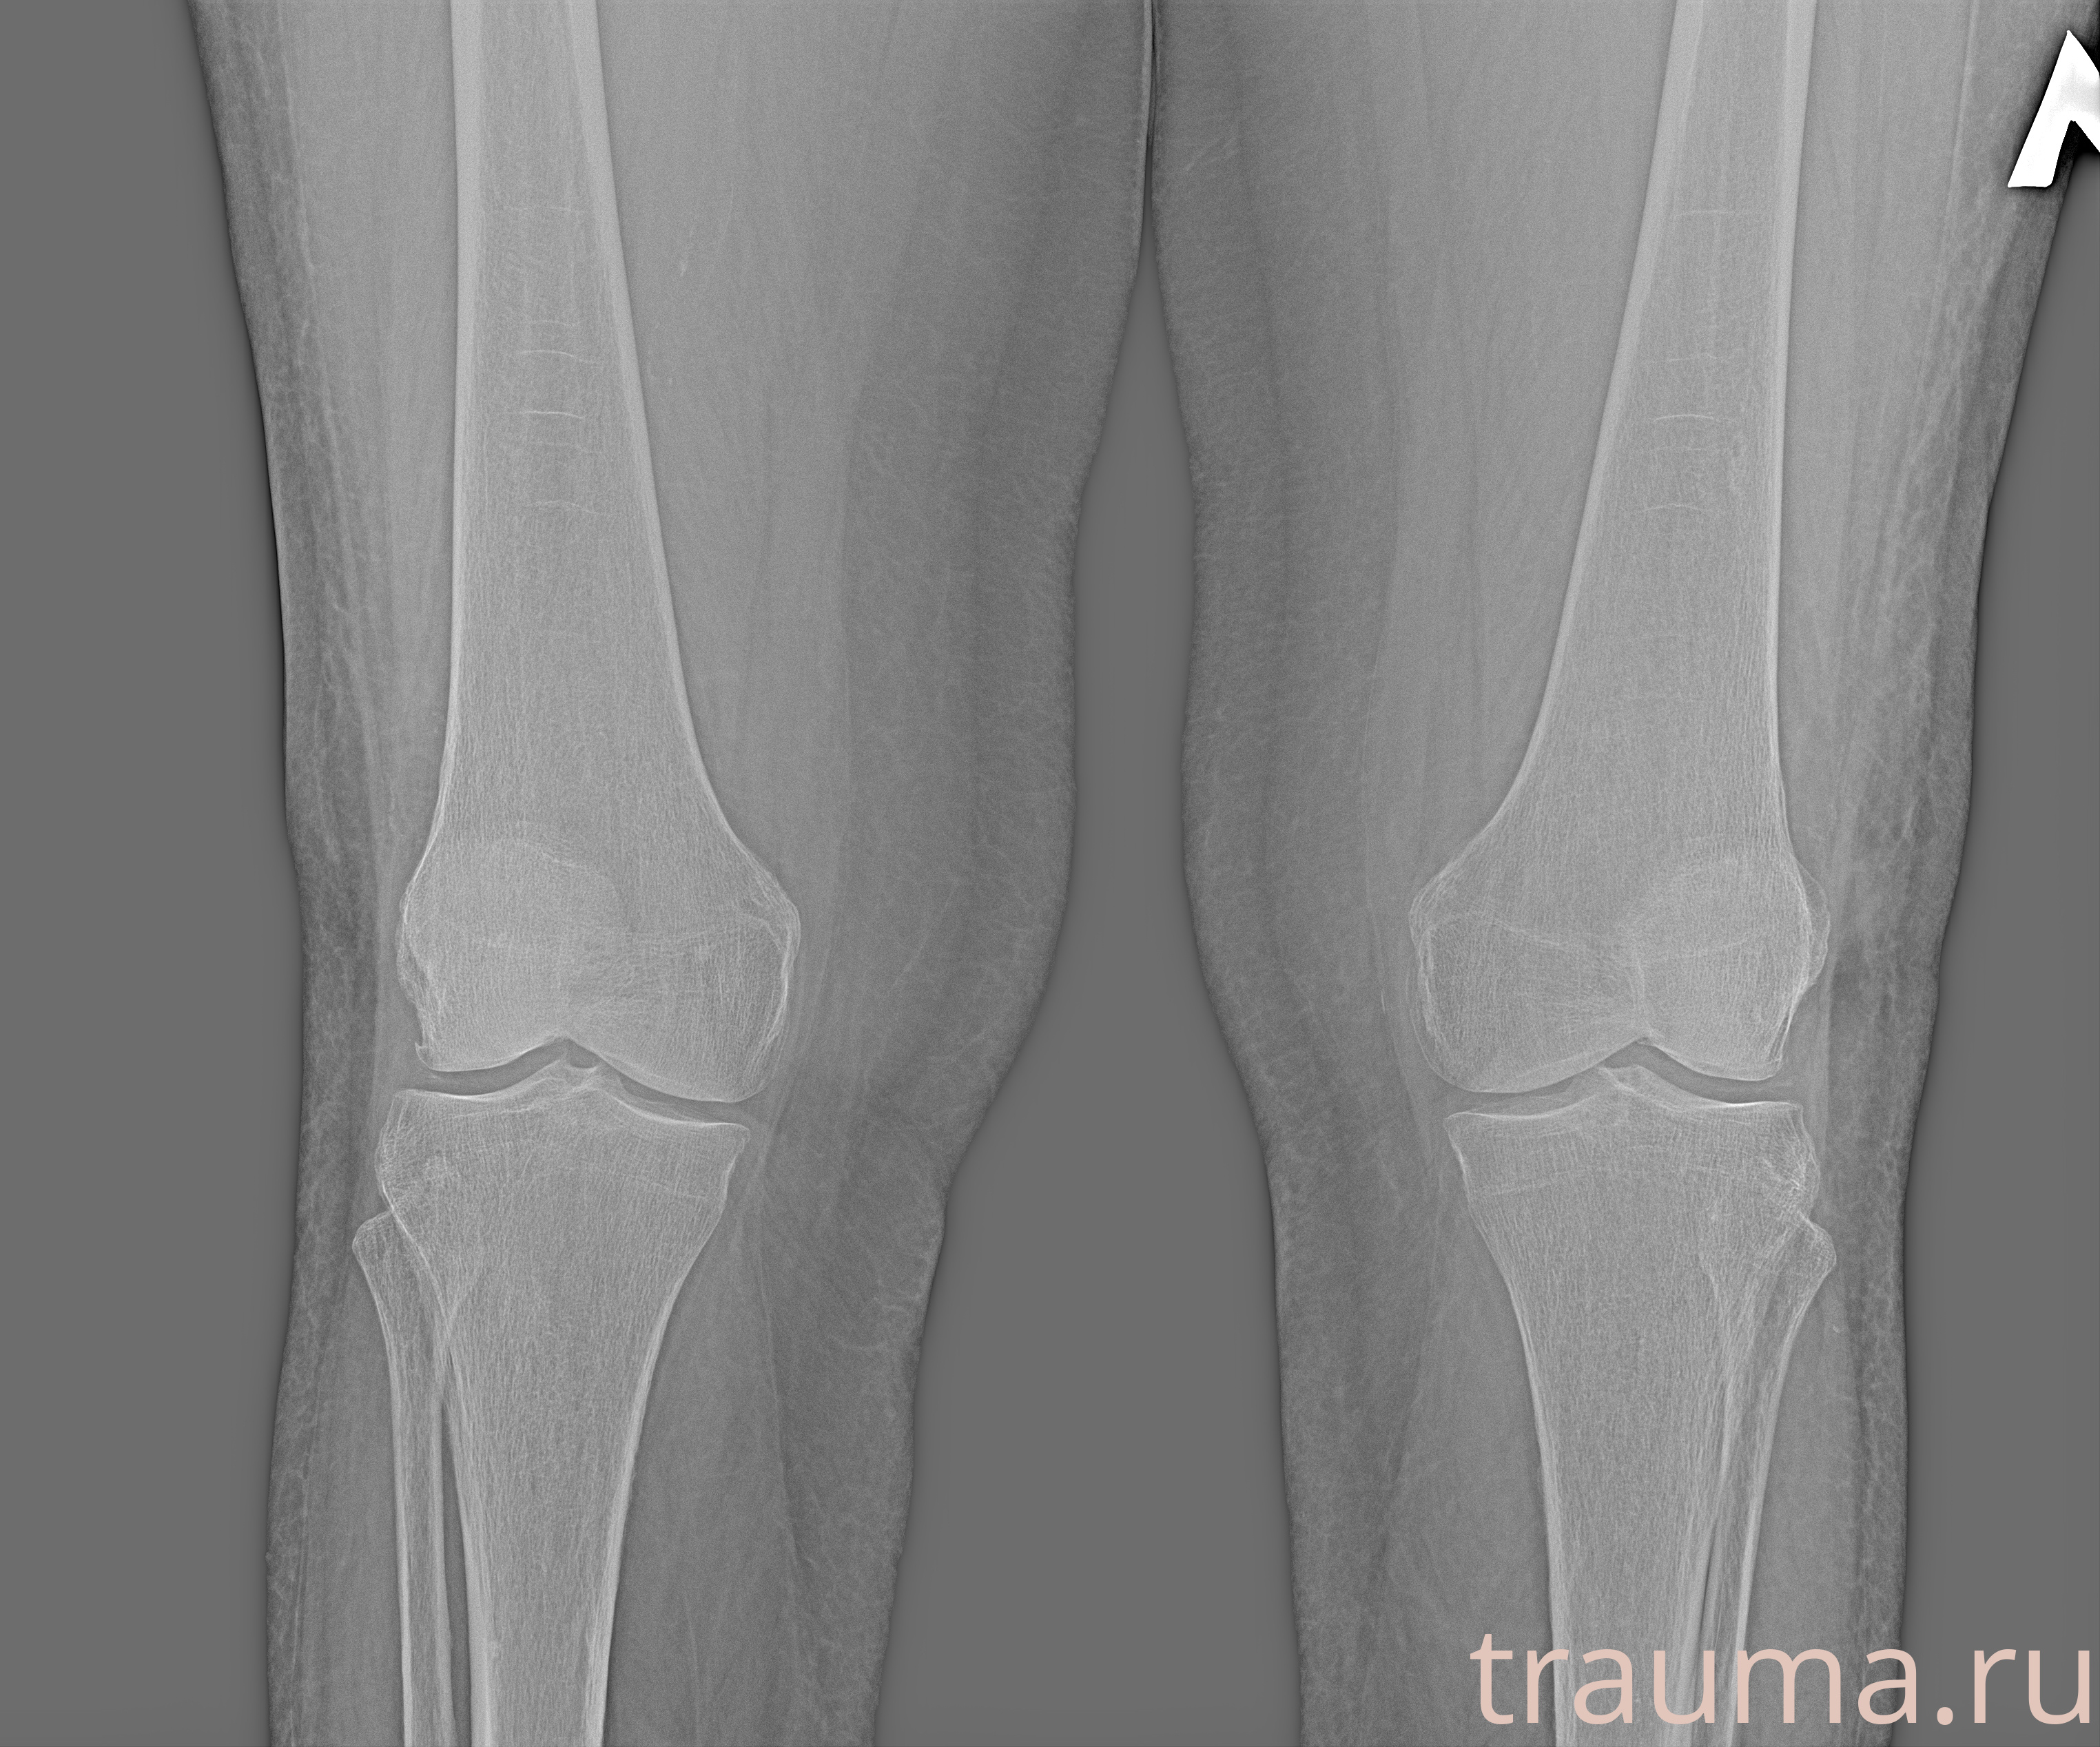

Рентгенограммы